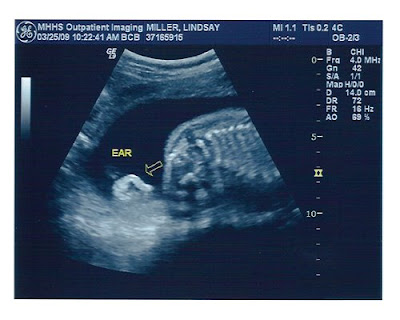

Latest Pictures of The Little Dude